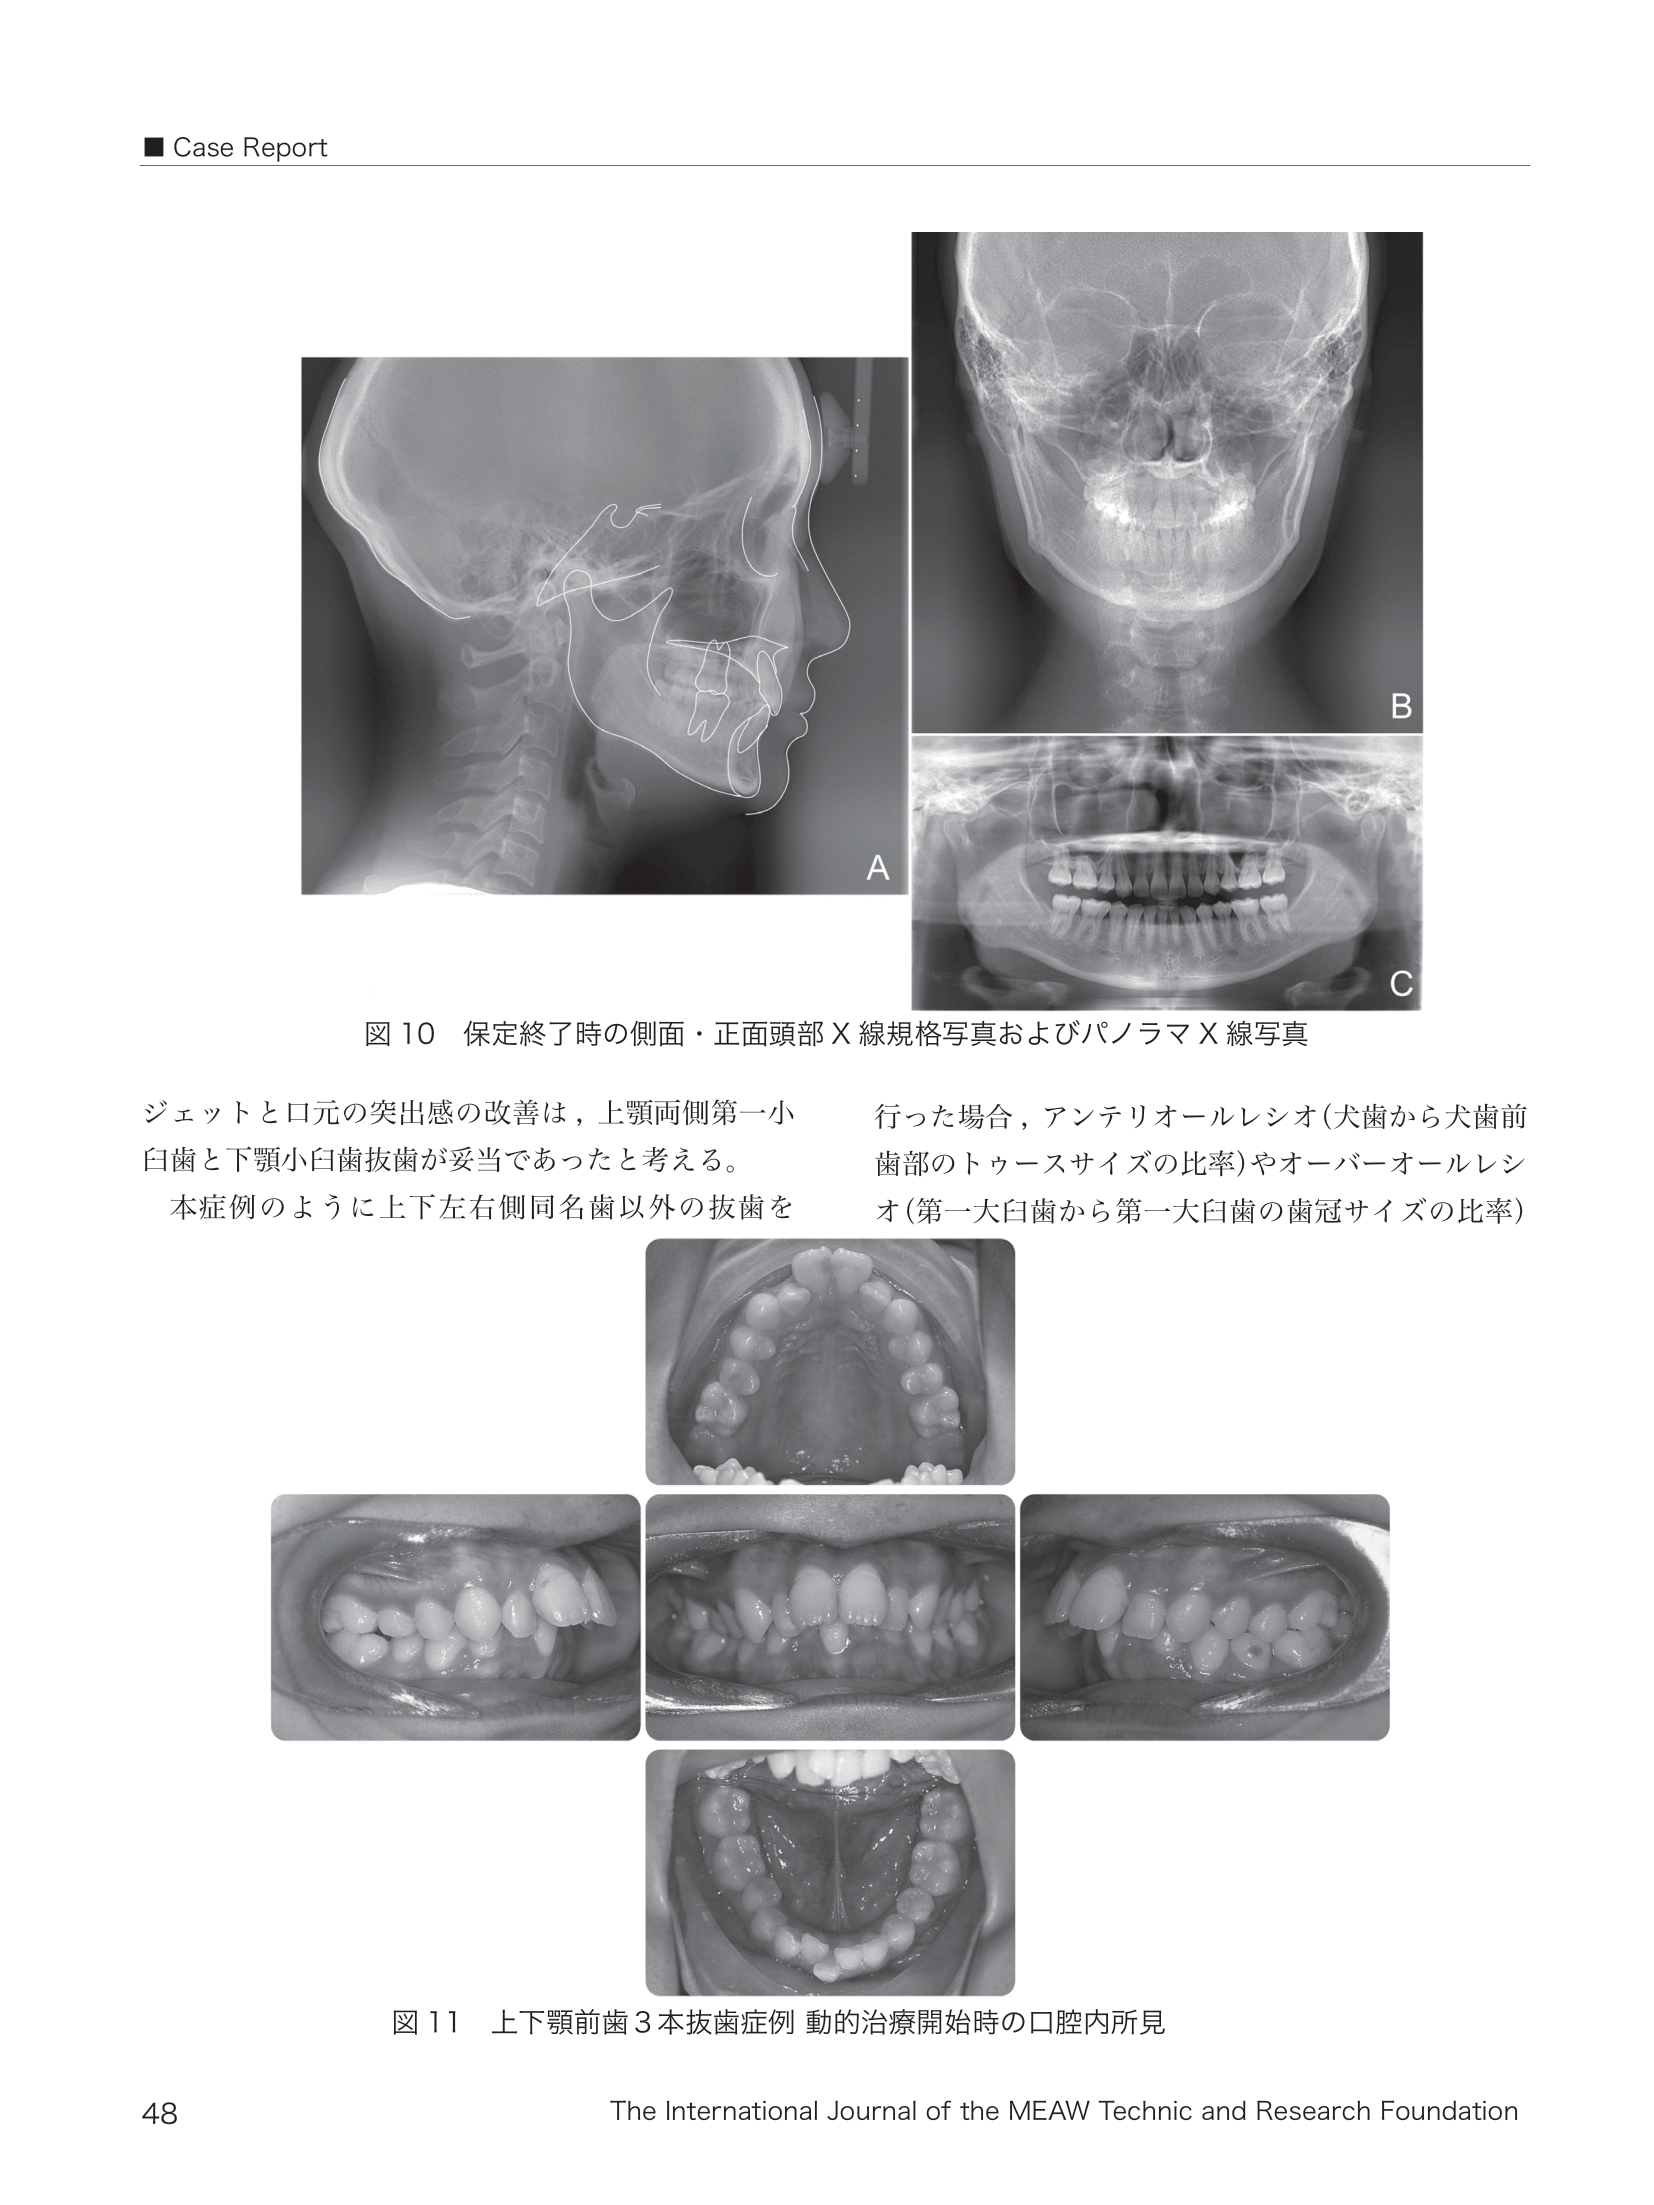

09.png